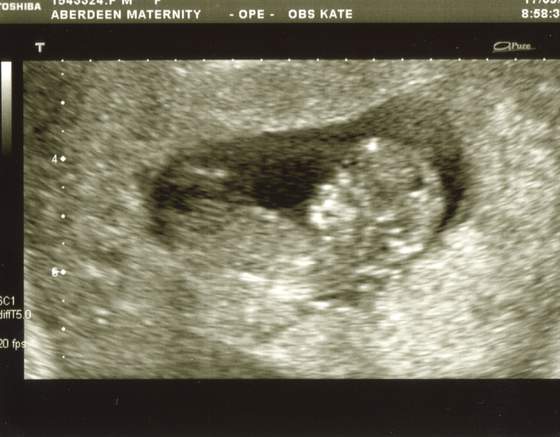

wszystko jest w najlepszym porzadku dzidzia rosnie ma 5 cm... serduszko bije jak szalone - dla mamusi![]()